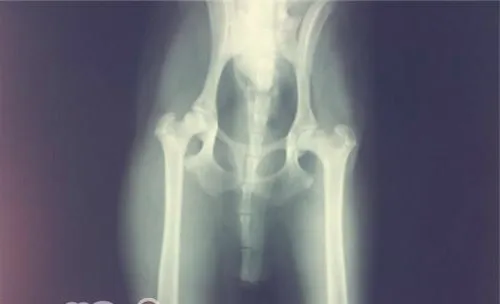

3、骨关节病:

由于肥胖而导致的体重高于正常,这会导致对骨关节的负担加重,使得一些骨关节病的

发病率会增加。这多表现在大型犬,当大型犬的幼犬在幼年时因能量摄入过多而导致肥胖后,会引发多种骨科疾病或加重髋关节发育不良的情况。同时,由于骨关节问题而导致的动物运动减少,导致能量消耗减少,而能量的摄入不便,会进一步加重肥胖,形成恶性循环。

髋关节发育不良